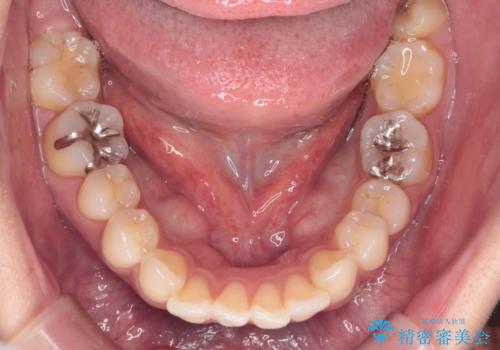

上顎前歯の突出を軽減 インビザラインによる抜歯矯正

- 上の前歯の突出感を気にして来院された患者様です。

目立たない装置を希望とのことで、上顎左右第一小臼歯を抜歯し、インビザラインにて矯正治療を行うこととしました。

インビザラインにて抜歯矯正を行うと、高頻度で奥歯が咬み合わなくなります。

また、抜歯スペースに向けて奥歯が移動する際、必ず傾斜して移動するため、仕上がりの咬み合わせはワイヤー矯正と比べて明らかに劣ります。